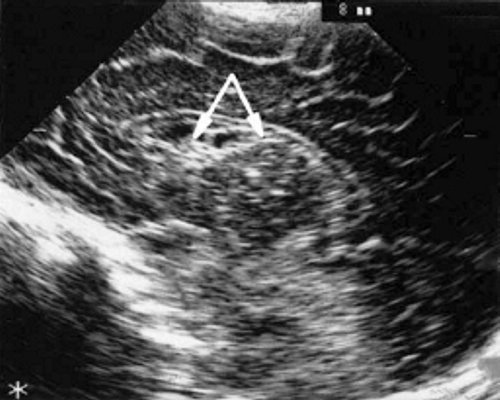

У детей этой группы при первом эхоэнцефалографическом исследовании были выявлены субэпендимально расположенные кистозные структуры на уровне таламо-каудальной вырезки (ТКВ) и (или) кпереди от нее диаметром от 0,3 до 1,1 см. У части новорожденных субэпендимальные кисты были представлены единой полостью с однородным или неоднородным содержимым, у других детей эти структуры напоминали соты, т. е. состояли из множества жидкостных включений, окруженных эхопозитивным ободком (рис. 3). Эти структурные особенности субэпендимальных кист, по-видимому, обусловлены разными стадиями резорбции. У 10 детей субэпендимальные кисты располагались в симметричных участках обоих полушарий, у 2 новорожденных - только в левом полушарии. У 3 детей, помимо субэпендимальных кист, расположенных в таламо-каудальной вырезке и (или) кпереди от нее, дополнительно выявлены субэпендимальные щелевидные кистозные структуры на уровне средних или передних отделов лобных рогов (см. рис. 3).

а) Правое полушарие. Стрелками обозначены субэпендимальные кисты, имеющие вид сот, расположенные в таламокаудальной вырезке и кпереди от нее.

б) Левое полушарие. Стрелками обозначены субэпендимальные кисты, имеющие вид сот, расположенные в таламокаудальной вырезке и кпереди от нее.

в) Правое полушарие. Стрелками обозначены субэпендимальные щелевидные кистозные структуры на уровне передних и средних отделов лобных рогов боковых желудочков.

г) Левое полушарие. Стрелками обозначены субэпендимальные щелевидные кистозные структуры на уровне передних и средних отделов лобных рогов боковых желудочков.